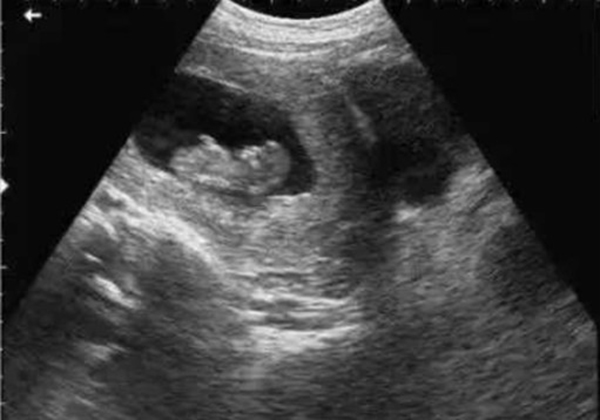

? 超聲檢查(B超/彩超):它利用超聲波的反射原理成像,就像“用聲音給身體拍照片”,沒有任何輻射。無論是孕期產(chǎn)檢(觀察胎兒發(fā)育)、腹部檢查(排查肝脾膽囊問題),還是甲狀腺、乳腺等淺表器官檢查,超聲都是首選。而且超聲檢查靈活便捷,還能實(shí)時(shí)動(dòng)態(tài)觀察器官運(yùn)動(dòng)(比如心臟跳動(dòng)、胎兒胎動(dòng)),是臨床中應(yīng)用最廣泛的“安全檢查”。

當(dāng)然,在非緊急情況下,醫(yī)生會(huì)優(yōu)先選擇超聲或MRI。比如孕婦產(chǎn)檢,超聲是核心檢查;嬰幼兒排查腦部問題,MRI是更安全的選擇。關(guān)鍵在于“權(quán)衡利弊”,而非“一刀切”拒絕。